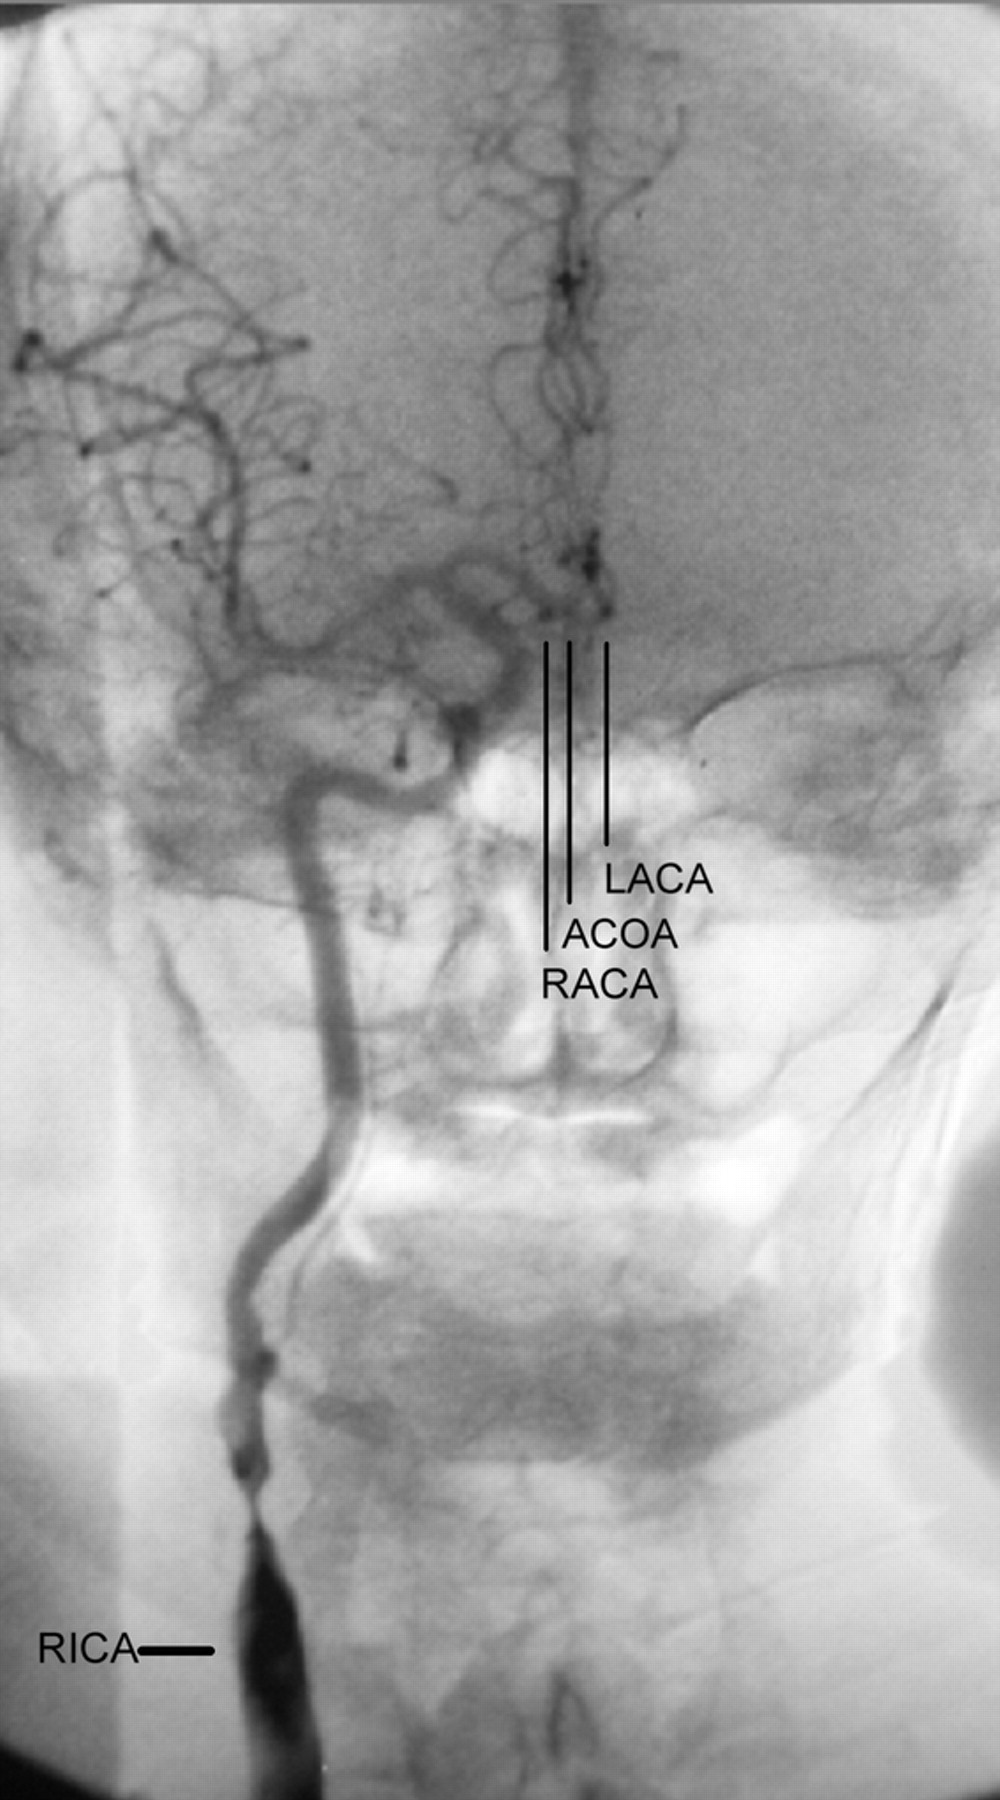

一个76岁的老人高血压和高胆固醇血症与多个事件,超过5天,两下肢麻木和软弱或右下肢。每一期持续了约30秒,通常发生在站。脑血管造影术显示关键右颈内动脉狭窄(图)。大脑前动脉都提供从狭窄的右颈动脉系统,导致两国的症状短暂下肢轻瘫。颈动脉手术后症状消失。发育不全的近端ACA发生在多达7%的人。1颈动脉狭窄的鉴别诊断应考虑瞬态下肢轻瘫。2